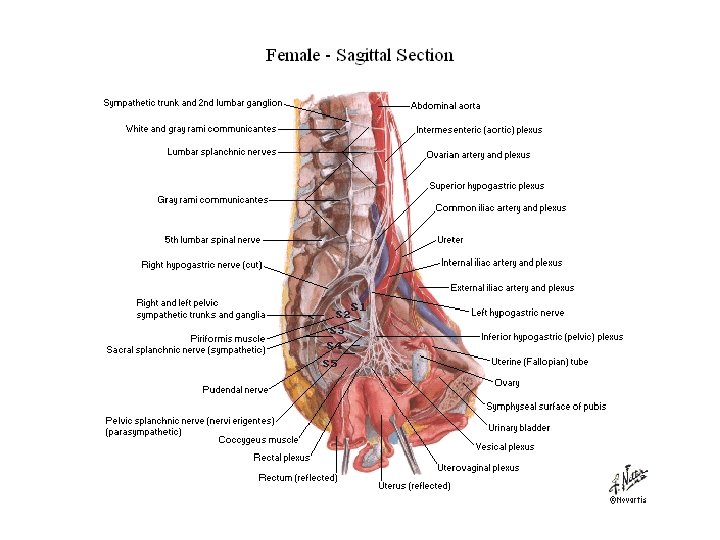

Anatomy: Pelvic Innervation • Pelvic splanchnic nerves from 2 nd to 4 th sacral nerves • Pudendal nerve supplies vulva and lower vagina

Pelvic Autonomics • Superior hypogastric plexus (presacral nerve) – Contains no parasympathetics • Hypogastric nerve • Inferior hypogastric plexus – Contains parasympathetic fibers from the pelvic splanchnics • Ganglion impar

Pelvik Organların Sinirleri

Pelvik Organların Sinirleri